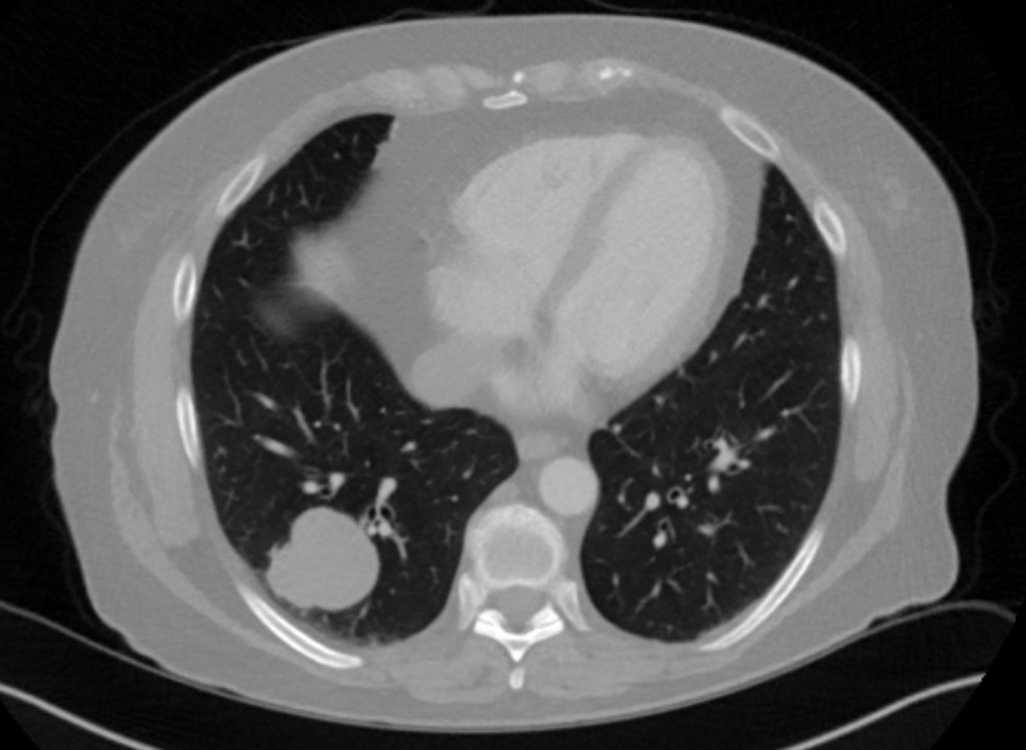

Figure 4_10X

Figure 5_20X